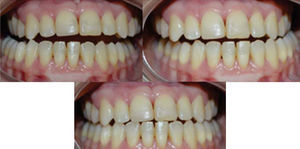

RESULTSThe arches were successfully correlated by eliminating the crossbite, the crowding was solved and the spaces were closed thus improving occlusal relationships and achieving molar and canine class I. The resulting overbite and overjet were adequate and remained under control. Periodontal status, aesthetics and function were favored (Figure 10) so the oral health and facial status of the patient was improved (Figure 11), emphasizing the harmony of a beautiful smile (Figure 12).

In the final cephalometry and in the superimposition, the skeletal changes were: initial facial depth: 94°, final: 92°; initial maxillary depth: 94°, final 95.4°; initial convexity: 0mm, final: 3.2mm; initial facial axis: 89°, final: 92.6°; initial Gn-GN/L1: 88°, final: 89°; initial SN/ U1: 100°, final 115° (Figure 13). It may be observed that a conservative treatment was performed since no surgical procedure was needed to correct the skeletal problem in addition to controlling periodontal health and improving the patient's esthetic conditions. However in order to achieve these results, the upper incisors were proclined (Figure 14).